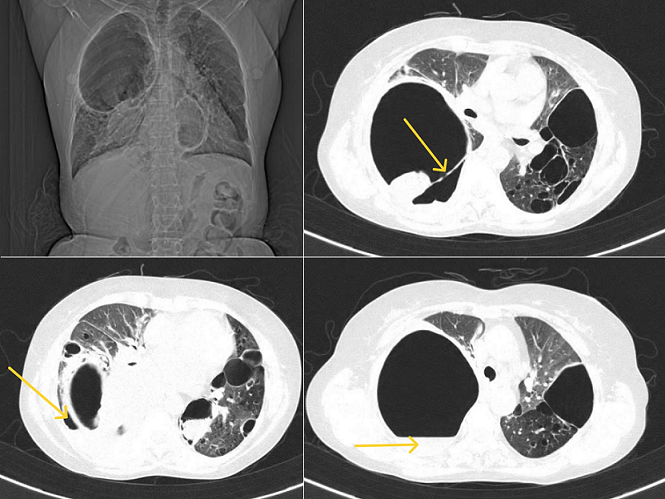

Apparent "double wall sign" in emphysematous bullae of the lung

A 52-year-old female patient came to the hospital with complaints of progressive breathlessness and dry cough on and off for 6 months, relieved with medications. High-Resolution Computed Tomography (HRCT) of the thorax showed a large thick-walled cavity showing air-fluid level in the right hemithorax and bilateral pan-acinar, paraseptal emphysematous changes with adjacent consolidation, and ground-glass opacities termed as bullae. A bulla is an air-containing structure bigger than 1 cm in diameter that develops inside the lung parenchyma as a result of disruption, dilation, and convergence of airspaces distal to terminal bronchioles. Massive bullous emphysema, when causing progressive dyspnea, is called "vanishing-lung syndrome." They are avascular radiolucent patches with curvilinear walls less than 1 mm in thickness, so challenging to identify radiologically from pneumothorax. A computed tomography (CT) scan is more sensitive for a precise evaluation, particularly when the bullae are veiled. The clinical image depicts a valuable "double-wall sign" that helps identify pneumothorax from adjacent giant bullae. When air is seen on either side of the bulla wall and parallel to the chest wall, the sign becomes obvious, and the lack of this sign reduces the probability of pneumothorax. A potential pitfall is the false visualisation of a double-wall sign when two bullae are adjacent to one another, sometimes simulating a pneumothorax and causing an apparent double-wall sign. However, a detailed study will show that the pleural gap is airless and the bulla wall is perpendicular to the chest wall. Hence, it is critical to distinguish between bullae and pneumothorax precisely to prevent iatrogenic pneumothorax from needless chest tube insertion.